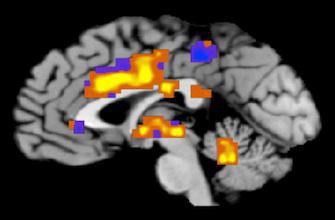

A quoi les malades d’Alzheimer peuvent-ils se raccrocher ? Les espoirs sont minces mais une piste de recherche est tout de même porteuse d’espoir. La stimulation cérébrale profonde pourrait en effet ouvrir des horizons, même si les recherches menées actuellement sont encore très préliminaires. « La stimulation cérébrale profonde, cela consiste à envoyer, à l’aide d’une électrode, un courant électrique dans une partie du cerveau qui va être activée ou bloquée », explique le Dr Marc Lévêque, neurochirurgien à l’hôpital de la Pitié-Salpêtrière à Paris. Concrètement, il faut faire un trou de quelques millimètres dans le crâne puis conduire une électrode jusqu’à une partie du cerveau qui aura été préalablement défini. Pour se frayer un chemin dans le cerveau, les neurochirurgiens pratiquent éveidemment l’intervention sous le contrôle d’un appareil de radio. Ensuite, l’électrode est implantée dans le cerveau et reliée à une sorte de pacemaker. Après plusieurs heures d’intervention chirurgicale, l’électrode envoie donc de manière permanente et constante un courant électrique.

Cette technique de stimulation cérébrale profonde est aujourd’hui utilisée relativement couramment dans la maladie de Parkinson. Dès que l’électrode est posée, les neurochirurgiens constatent – alors que le patient est encore entre leurs mains – que les tremblements s’arrêtent. Les recherches progressent aussi dans le traitement de la dépression sévère et des troubles obsessionnels compulsifs. En revanche, ce n’est que récemment que la technique a été expérimentée dans la maladie d’Alzheimer.

En fait, c’est l’équipe canadienne du Pr Lozano qui a découvert, un peu par hasard, les potentiels de la stimulation cérébrale profonde dans la maladie d’Alzheimer. Ces médecins tentaient de réveiller le sentiment de satiété d’une personne obèse en stimulant l’hypothalamus. « Au lieu d’une telle sensation, le malade, pendant l’intervention, a décrit avec acuité une scène survenue trente ans plus tôt, écrit Marc Lévêque dans son livre qui vient de sortir, intitulé « Neurochirurgie » (1). Les tests neuropsychologiques ont mis en évidence une nette amélioration de la mémoire biographique à chaque stimulation ».

Une découverte faite par hasard mais tellement étonnante que le Pr Lozano n’en est pas resté là. Un essai clinique a été lancé sur six patients. Un an plus tard, les résultats aux tests test d’évaluation des fonctions cognitives et de la capacité mnésique montraient une stabilisation des fonctions cognitives et de la mémoire chez 1 patient, une stabilisation chez 2 et la poursuite du déclin chez les 3 autres.